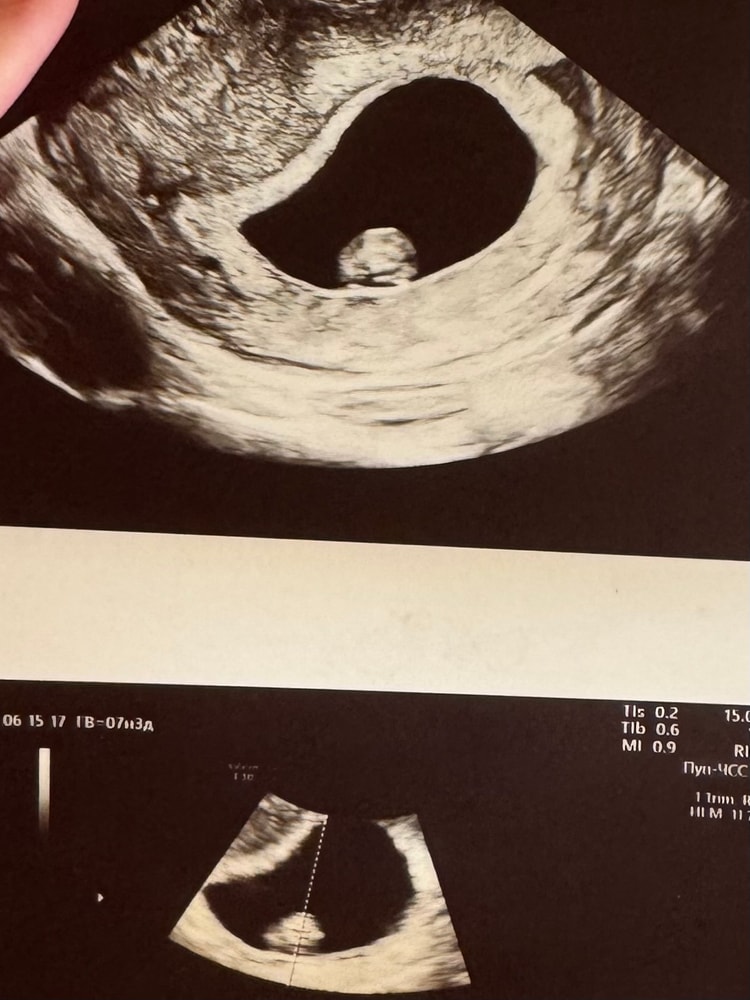

Можно и мне узнать кто будет 6-7 недель

05.01.2021

Гүлнұр Бақыт, здравствуйте, девочка родилось 😊долго ответа ждала 😁

Анжелика Плаксина, то есть узи был по животу? Проверяю метод. Пусть растет на радость!!!!